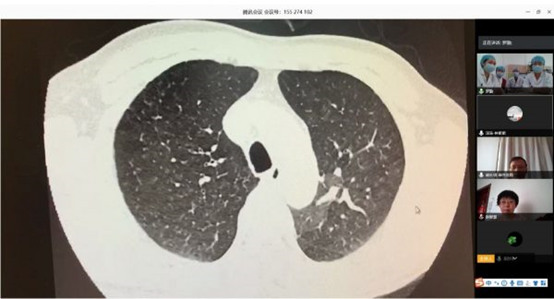

北阜和深阜肺血管病房在線查房

根據(jù)衛(wèi)健委新冠肺炎疫情防控工作總體部署以及醫(yī)院要求, 3月16日,北阜肺血管與血栓一病區(qū)和深阜肺血管病房已同步開(kāi)始有序收治患者,開(kāi)展包括右心導(dǎo)管、肺動(dòng)脈造影及慢性血栓栓塞性肺動(dòng)脈高壓患者的肺動(dòng)脈球囊擴(kuò)張術(shù)等手術(shù)在內(nèi)的肺血管病所有診治。為減少新冠肺炎疫情傳播風(fēng)險(xiǎn),保證深圳肺動(dòng)脈高壓患者得到最佳診療方案,北阜和深阜兩地肺血管病房充分利用“互聯(lián)網(wǎng)+醫(yī)療”的優(yōu)勢(shì)作用,開(kāi)展遠(yuǎn)程線上查房,對(duì)每位患者資料進(jìn)行詳細(xì)分析,確定診治方案,使深圳的患者在疫情特殊時(shí)期可得到與平時(shí)同樣的醫(yī)療服務(wù)。